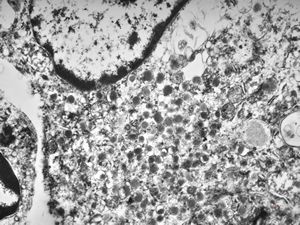

M,29y. | jejunum - lipid malabsorption

jejunum … lipid malabsorption

Whipple disease - lipid malabsorption